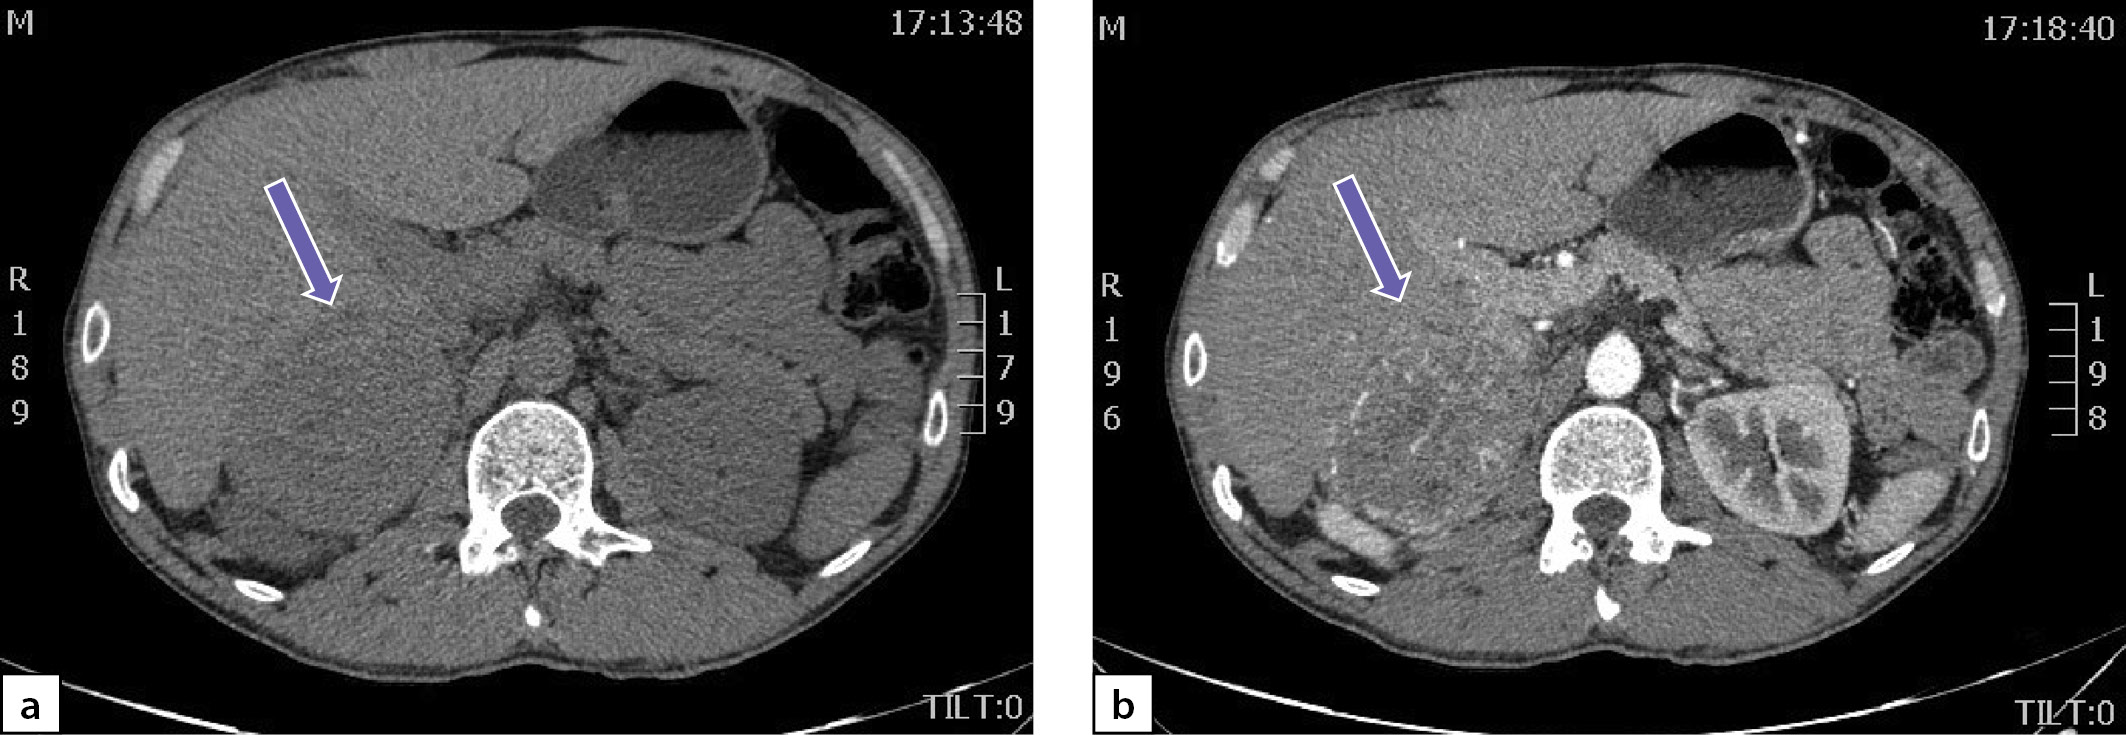

По данным мультиспиральной компьютерной томографии (МСКТ) брюшной полости и забрюшинного пространства с в/в контрастным усилением: в правом надпочечнике, занимая все его пространство, определяется объемное образование с четкими контурами, размерами 80х75х85 мм, плотностью в артериальную фазу 66 НU, в венозную фазу 69 НU, в паренхиматозную фазу 62 НU, в отсроченную до 51 НU (рис. 2 a, b). Кроме того, в забрюшинном пространстве, слева, с деформацией левой почки на уровне средней трети, определяется объемное образование размерами 49х37х47 мм, преимущественно мягкотканой плотности 31 НU, неоднородной структуры, с наличием участков пониженной плотности. Накопление контрастного вещества в артериальную фазу 86 НU, в венозную фазу 112 НU, в паренхиматозную фазу 85 НU, в отсроченную до 62 НU (рис. 3 a, b).

Рисунок 2. Феохромоцитома правого надпочечника:

а) нативная фаза; b) после введения контрастного препарата.

Figure 2. Pheochromocytoma of the right adrenal gland:

a) native phase; b) after administration of a contrast agent.

Рисунок 3. Образование забрюшинного пространства слева:

Figure 3. Formation of the retroperitoneal space on the left:

a) native phase; b) after administration of a contrast agent

Учитывая молодой возраст пациента, злокачественный КТ-фенотип выявленных образований и наличие артериальной гипертензии, у пациента были все основания для исключения ФХЦ.

В существующих клинических рекомендациях по диагностике и лечению НФ-1 нет указания о необходимости проведении рутинного скрининга на ФХЦ/ПГ при НФ-1 [11]. Тем не менее необходимо отметить, что клинические рекомендации датированы 2007 г., в то время как более поздние исследования, показавшие высокую частоту ФХЦ/ПГ при НФ-1, были проведены позже. По мнению Képénékian L. et al., скрининг ФХЦ/ПГ рекомендовано проводить всем пациентам с НФ-1 старше 40 лет [17], в то время как Gruber L.M. et al. рекомендуют проведение биохимических тестов на выявление ФХЦ/ПГ у пациентов любого возраста в момент диагностики НФ-1 и затем каждые 3 года в течение всей жизни [17][20]. В нашем случае у пациента с клиническими признаками НФ-1 повышение АД фиксировалось с 26 лет (т.е. моложе 40 лет). Однако поводом для исключения гиперкатехоламинемии стали случайно выявленные образования правого надпочечника и забрюшинного пространства слева в возрасте 36 лет. По данным МСКТ, образования были сходной высокой нативной плотностью (>30 НU) и значительных размеров (>4 см), что соответствовало злокачественному КТ-фенотипу и было патогномонично для ФХЦ/ПГ [30][31]. Данные лабораторного обследования однозначно подтвердили наличие ФХЦ/ПГ у нашего пациента с НФ-1, но нельзя было сделать однозначного заключения в отношении топического диагноза. Образование правого надпочечника имело большие размеры, «худшие» параметры нативной плотности и процента вымывания контрастного вещества, поэтому первым этапом была произведена лапароскопическая адреналэктомия с опухолью справа, гистологически верифицирована ФХЦ. После хирургического лечения у пациента спонтанно нормализовалось АД без антигипертензивной терапии, значительно снизились (однако полностью не нормализовались) уровни метанефринов и норметанефринов.

Образование забрюшинного пространства слева, по данным МСКТ, не исходило из надпочечника, однако высокие плотностные характеристики, отсутствие полной нормализации уровней метанефринов после удаления феохромоцитомы справа и прогрессирующий рост не позволили полностью исключить параганглиому. Кроме того, признаки сдавления левой почки и значительные размеры образования являлись самостоятельными показаниями для хирургического лечения. В связи с этим вторым этапом было произведено лапароскопическое удаление образования забрюшинного пространства слева, которое гистологически было верифицировано как нейрофиброма забрюшинного пространства. Уровни свободных метанефринов и норметанефринов в суточной моче полностью нормализовались после второй операции. Было высказано предположение, что некоторое повышение уровня метанефринов и норметанефринов, сохранявшееся после первой операции, могло быть связано со значительным сдавлением левого надпочечника нейрофибромой.